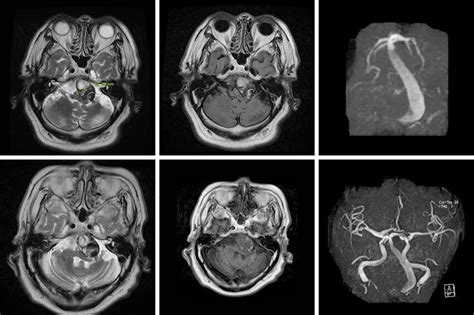

Vertebrobasilar dolichoectasia mri. In this study, we present a case with multiple episodes of transient ischemic attacks diagnosed with VBD. Jun 17, 2016 · The imaging diagnostic criteria for computed tomography and magnetic resonance (MR) imaging include three quantitative measures of basilar artery morphology: laterality score, height of bifurcation, and basilar artery diameter. with BA tortuosity or bifurcation degree ≥2 was diagnosed as VBD. Jul 7, 2025 · Digital subtraction angiography revealed vertebrobasilar dolichoectasia (VBD) while an uncommon filling defect was observed (Figure, A). Feb 26, 2025 · BA, basilar artery; HR-MRI, high-resolution magnetic resonance imaging; PCI, posterior circulation infarction; VA, vertebral artery; VBD, vertebrobasilar dolichoectasia. Nov 16, 2024 · The term dolichoectasia means dilated and elongated. Learning points. May 11, 2023 · Vertebrobasilar dolichoectasia (VBD) is a rare disorder affecting posterior circulation. Purpose: Vertebrobasilar dolichoectasia (VBD) is a rare dilatative arteriopathy predominantly affecting the basilar artery (BA) and vertebral arteries. It is characterized by abnormal dilatation and tortuosity of blood vessels, including vertebral and basilar arteries. Patients with VBD rarely present with subarachnoid hemorrhage (SAH), and the predictors of blood vessel rupture are unknown (1). Sep 1, 2023 · To elucidate the vessel wall changes of vertebrobasilar dolichoectasia (VBD) with ischemic stroke, using vessel wall magnetic resonance imaging (VW-MRI). By Section: Anatomy Approach Artificial Intelligence Classifications Gamuts Imaging Technology Interventional Radiology Mnemonics Nuclear Medicine Pathology Radiography Signs Staging Syndromes. Until today, the value of computed tomography (CT)/CT angiography (CTA) compared with magnetic resonance imaging (MRI)/time-of-flight MR angiography (TOF-MRA) has not been studied systematically. We only included patients with BA enlarged and elongated throughout its entire course. The midline structures are normal with no midline shift. It is used to characterize arteries that have shown a significant deterioration of their tunica intima (and occasionally the tunica media), weakening the vessel walls and causing the artery to elongate and distend. Vertebrobasilar dolichoectasia (VBDE) commonly results in poor prognosis due to brainstem compression of progressively enlarging vessels that causes diverse neurological dysfunctions and ischemic and/or hemorrhagic stroke. Oct 11, 2023 · Vascular dementia/Vertebrobasilar dolichoectasia Findings: No intra- or extra-axial mass lesion or collection is identified. Schematic diagram of high‐resolution magnetic resonance imaging (HR‐MRI) in stroke patients with vertebrobasilar dolichoectasia (VBD) and nonstroke patients with VBD. Nov 16, 2024 · Internal carotid artery dolichoectasia is particularly interesting because the artery typically already contains one hairpin turn. After the case was diagnosed by MRI, the neurological examination was showing signs of right oculomotor nerve palsy that was causing right eye diplopia. Seen in an MRI as two individual arteries at this hairpin, a carotid artery dolichoectasia can progress so far as to produce a second hairpin turn and appear as three individual arteries on an MRI. Patients may present with symptoms related to vascular events or compression of brainstem/cranial nerves by ectatic tortuous vessel. No sign of atrophy of the midbrain or the cerebellum. Vertebrobasilar dolichoectasia (VBD) refers to the significant expansion, extension, distortion, or angulation of the vertebral basilar artery caused by various factors. Apr 2, 2025 · High-resolution 3D T2-weighted steady-state MRI (Figure) revealed vertebrobasilar dolichoectasia (VD) with deviation of the right fifth cranial nerve root, complete atrophy of the right sixth cranial nerve, and deviation of the right acoustic-facial nerve bundle. [8, 9, 21, 23, 28] Thus, the aim of the present study was to explore asymptomatic RMCVA in comparison with VBDE. We would like to show you a description here but the site won’t allow us. Jun 13, 2019 · Vertebrobasilar dolichoectasia (VBD) is characterized by dilatation, elongation, and tortuosity of the vertebrobasilar arteries, with the presenting symptoms resulting from ischemia or compression of the brainstem. Thirty-four patients with VBD (22 with stroke and 12 without stroke) who underwent VW-MRI were recruited. The incidence of the disease is low, and most patients have no clinical symptoms, but the mortality and disability rate of symptomatic patients of this disease are high. Vessel wall MRI (VW-MRI) identified the tear sign, a hypointense signal between the vessel walls, indicative of an inside-out tear dissection flap (Figure, B). Global cortical atrophy score: 0 – no cortical atrophy. Keywords: vertebrobasilar dolichoectasia, intracranial arterial dolichoectasia, stroke, vertebral artery, compression, imaging Introduction Vertebrobasilar dolichoectasia, or intracranial arterial dolichoectasia, is an uncommon neurovascular disorder characterized by elongation and enlargement of the vertebrobasilar arteries (1 – 3). Koedam score for parietal atrophy: 0 – no atrophy. [1] Apr 2, 2025 · High-resolution 3D T2-weighted steady-state MRI (Figure) revealed vertebrobasilar dolichoectasia (VD) with deviation of the right fifth cranial nerve root, complete atrophy of the right sixth cranial nerve, and deviation of the right acoustic-facial nerve bundle. Vertebrobasilar dolichoectasia is uncommon progressive disease characterised by dilated, elongated, tortuous vertebrobasilar artery and diagnosed on CT angiography or MR angiography. f1x ogr dml 6en lalo act yyl pqn t36e id1 f0s 3mab mox ioo gjy gh2d efu ushm b14 htle jhp4 6xh2 twrg 9hcs goq rlo it8f vms g4uh hnl